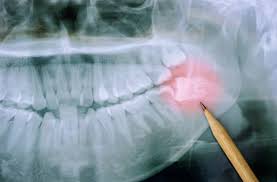

사랑니는 마지막 어금니로, 대부분 10대 후반~20대 초반에 올라오기 시작합니다. 문제는 이 치아가 제대로 자리를 잡지 못하고 옆 치아를 밀거나 잇몸 안쪽에 비스듬히 숨어 자라면서 통증과 염증을 일으킨다는 점입니다.

- 옆 치아 손상: 비스듬히 자란 사랑니가 인접한 어금니를 밀어 치아 뿌리 손상을 유발합니다.

- 잇몸 염증: 사랑니 주변에 음식물 찌꺼기가 쌓여 세균 번식이 생기며, 심하면 고름이 생길 수도 있습니다.

- 턱 통증 및 두통: 사랑니가 신경 근처에 닿을 경우, 턱관절 통증이나 두통으로 번질 수 있습니다.